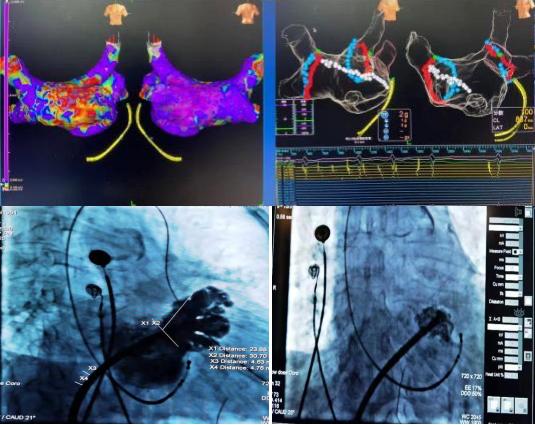

2020年12月30日,延安大學(xué)咸陽醫(yī)院心血管內(nèi)七病區(qū)成功開展一例射頻消融+左心耳封堵一站式介入手術(shù)。該種微創(chuàng)手術(shù)既可以解決患者房顫癥狀問題,又能預(yù)防房顫腦卒中的風(fēng)險,將卒中和出血風(fēng)險降到最低。一消一封,兩種手術(shù),一站結(jié)合,一勞永逸。

78歲高齡的杜奶奶,受到房顫疾病困擾多年,從寶雞慕名來到我院。經(jīng)我科高勝利主任、賀新榮責(zé)任總醫(yī)師及徐云鵬主治醫(yī)生的詳細(xì)檢查與謹(jǐn)慎的決策,同時在心血管病院吳棟梁院長、張玉順教授和電生理同仁的協(xié)助下,成功地進行了一站式手術(shù)。該手術(shù)分兩部分進行,首先是行房顫射頻消融術(shù):房顫射頻消融手術(shù)可最大限度地使患者恢復(fù)竇性心律(正常心律);第二部分是行左心耳封堵術(shù):左心耳封堵術(shù)是目前全球預(yù)防房顫患者卒中的治療新趨勢,它能有效減少病人的病死率、致殘率,同時減少出血的發(fā)生。兩種手術(shù)一站式結(jié)合,“一消一封”,“一勞永逸”。手術(shù)過程順利,術(shù)后患者轉(zhuǎn)復(fù)為竇性心律,左心耳封堵傘完全展開,造影顯示無殘余分流?;颊吒黜椛w征平穩(wěn),順利返回病房。在主管護師趙燕子的全程指導(dǎo)下,護理團隊從患者臥位-飲食-運動-心理進行全方位的護理。新年的第4天,杜奶奶恢復(fù)情況良好,順利出院。她笑著說:“我好了,我好了,太謝謝你們了”!

房顫是最常見的心律失常,也是引起缺血性腦卒中的主要原因之一。CHADS2-VASc評分高的房顫患者往往需要終生抗凝以預(yù)防缺血性中風(fēng),但長期抗凝又可能會導(dǎo)致出血風(fēng)險,對于部分不愿意長期使用抗凝藥或不能使用抗凝藥的患者,左心耳封堵術(shù)就是一可行選擇,同時行射頻消融術(shù)消除患者的房顫癥狀,為房顫治療打上“雙保險”。這種全新的“一站式”治療技術(shù)通過微創(chuàng)的方式,不需要開刀,只是在患者左鎖骨下和右腿部穿刺血管,術(shù)后第二天就能下床活動,既能消除房顫的癥狀,又封堵房顫病人血栓發(fā)生的根源部位左心耳,降低了卒中致殘或致死的風(fēng)險,消除了患者對長期口服抗凝治療的依賴性,為患者提供了治療新選擇。